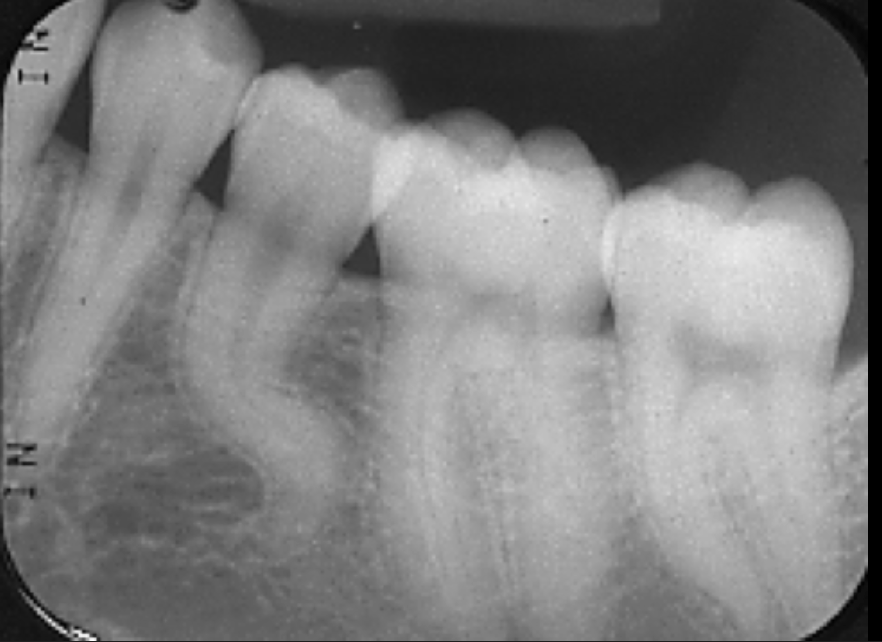

If the contacts get worse as we move back in the mouth, what radiograph error is happening?

It means we are rotated mesial-distally.

On a molar bitewing, what contacts should be open?

All contacts surrounding the 2nd molar

On a premolar bitewing, what contacts should be open?

All contacts surrounding the 2nd premolar

What do we want to see in the front of the molar bitewing radiographs?

-Between the first furcation (where the roots divide) of the 3rd molar and half the 2nd premolar

What do we want to see in the front of the premolar bitewing radiographs?

-Between half the canine and the pulp chamber of the 1st premolar